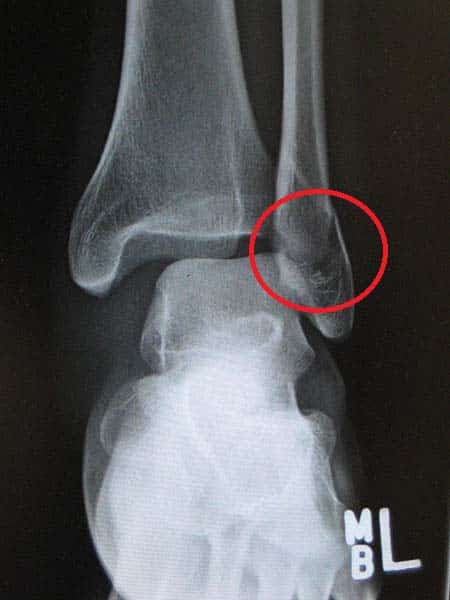

The fibula is a bone located within the lateral aspect of the leg. Its main function is to act as an attachment for muscles, and not as a weight-bearer. It has three main articulations: Proximal tibiofibular joint – articulates with the lateral condyle of the tibia. Distal tibiofibular joint – articulates with the fibular notch of the tibia. Ankle joint – articulates with the talus bone of the foot. In this article, we shall look at the anatomy of the fibula – its structure, bony landmarks and clinical relevance. Adapted from work by Anatomography [CC BY-SA 2.1 jp], via Wikimedia Commons Fig 1Overview of the position of the fibula within the leg. Pro Feature - 3D Model You've Discovered a Pro Feature Access our 3D Model Library Explore, cut, dissect, annotate and manipulate our 3D models to visualise anatomy in a dynamic, interactive way. Learn More Bony Landmarks Proximal At the proximal end, the fibula has an enlarged head, which contains a facet for articulation with the lateral condyle of the tibia. On the posterior and lateral surface of the fibular neck, the common fibular nerve can be found. Shaft The fibular shaft has three surfaces – anterior, lateral and posterior. The leg is split into three compartments, and each surface faces its respective compartment e.g anterior surface faces the anterior compartment of the leg. Distal Distally, the lateral surface continues inferiorly, and is called the lateral malleolus. The lateral malleolus is more prominent than the medial malleolus, and can be palpated at the ankle on the lateral side of the leg. Adapted from work by OpenStax College [CC BY 3.0], via Wikimedia Commons Fig 2Anatomical landmarks of the fibula Clinical Relevance Fractures of the Fibula At the ankle, the lateral malleolus of the fibula is prone to fracture. There are two main ways in which this occurs. The first way is by forced external rotation of the ankle. This force of the talus against the bone causes a spiral fracture of the lateral malleolus. The other, less common way, by the foot being twisted outwards (called eversion). Again, the talus presses against the lateral malleolus, and this time causes a transverse fracture. By James Heilman, MD [CC-BY-SA-3.0], via Wikimedia Commons Fig 3Fracture of the lateral malleolus. Do you think you’re ready? Take the quiz below Pro Feature - Quiz The Fibula Question 1 of 1 Submitting... Skip Next Rate question: You scored 0% Skipped: 0/1 1800 More Questions Available Upgrade to TeachMeAnatomy Pro Challenge yourself with over 1800 multiple-choice questions to reinforce learning Learn More Rate This Article